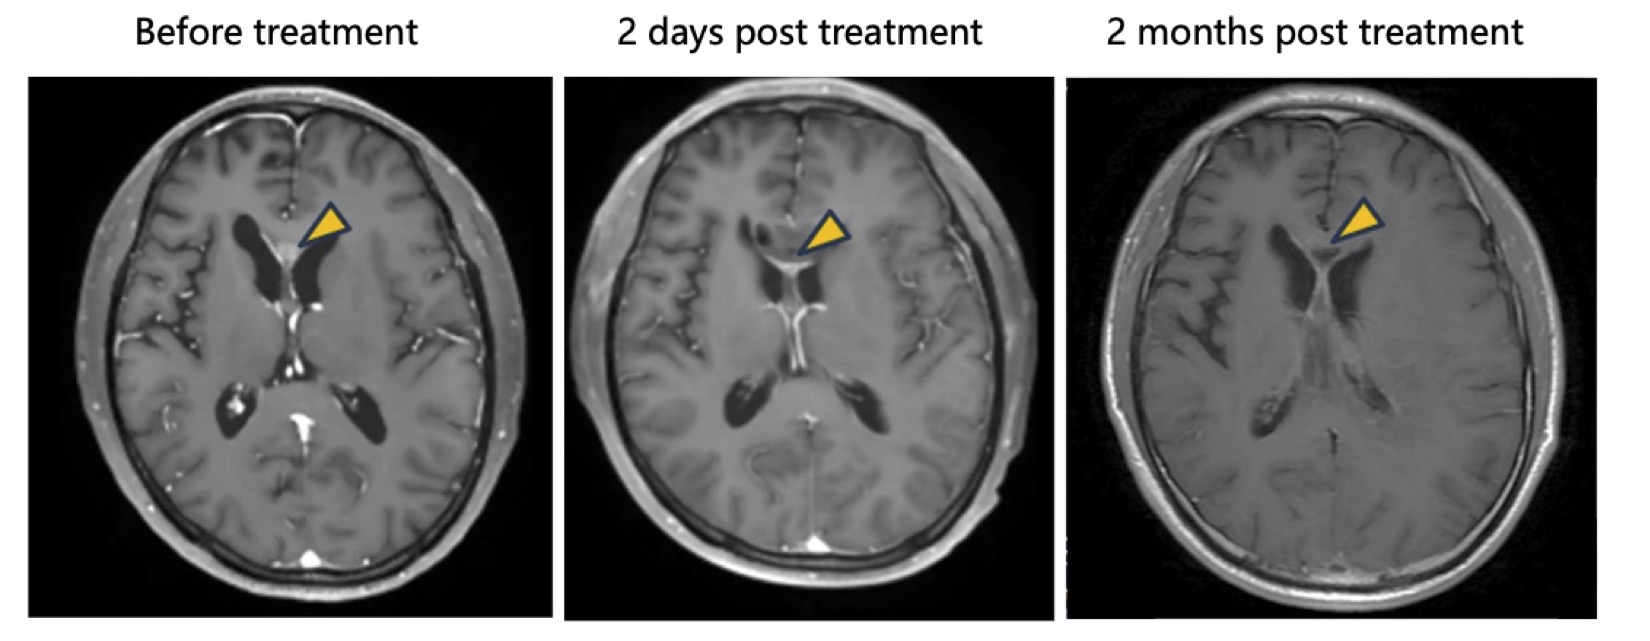

- Complete Response: In one patient receiving tumor resection followed by intracavitary NXL-004 injection, postoperative imaging showed progressive tumor reduction, ultimately resulting in complete radiographic disappearance, achieving a complete response (CR).